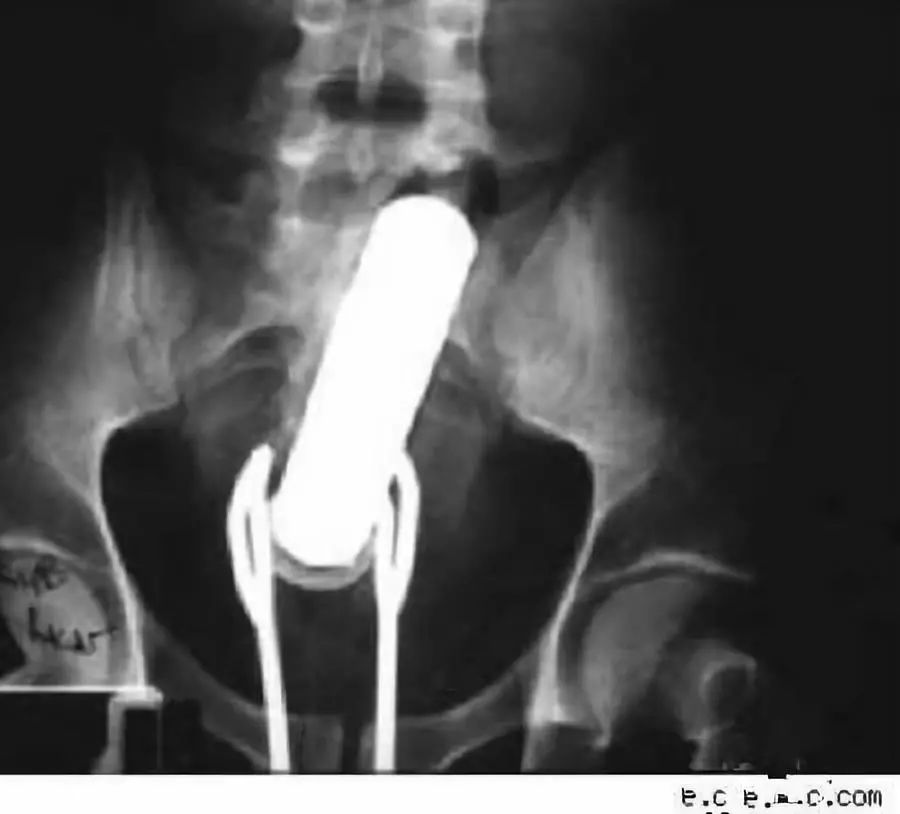

肛肠和泌尿科的x光片藏着成年人最深的秘密

图片尺寸900x814